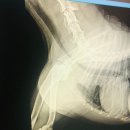

관리 해줬을까 하는 걱정이 좀 있네요.. 일단 생각보다 빨리 회복 하는 것 같아 나래동물의료센터에 진심으로 감사드립니다. 그리고 버텨주는 저희 강아지에게도...슬개골 수술을 고민하는 누군가, 청주에 거주하는 견주분들 한명에게라도 병원 선택과 수술기록이도움이 되길 바라며, 이만 마치겠습니다. 궁금한 점이...

이런 부분까지 신경 써주셔서 더 믿음이 갔어요 💕 청주 동물병원 '청주 나래 동물 의료센터' 처음 병원 선택에서는 시행착오가 있었지만, 지금은 청주 나래...잘하는 청주 동물병원을 찾고 계신다면, 저는 자신 있게 청주 나래 동물 의료센터를 추천드려요 🐾✨ 실제 경험한 찐 후기 입니다!! 우리 러블이 얼른 회복...

월요일-금요일 10:00-22:00 토요일, 일요일 10:00-19:00 (12:45-14:00 휴게시간) (설날 및 추석, 연휴기간 3일휴무) 평일에 밤 늦은시간까지 하는 병원 많지않은데 나래동물의료센터는 야간 밤10시까지 운영해요. (21:30까지 접수) 외과원장 전공의(풀타임), 정형외과 책임집도의 대학병원 근무경력 집도의가 있는 곳...